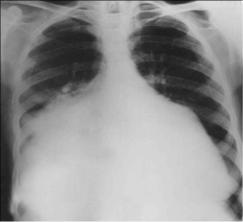

Хроническая ревматическая болезнь сердца - заболевание,

характеризующееся поражением сердечных клапанов в виде поствоспалительного краевого фиброза клап анных створок или порока сердца (недостаточность и/или стеноз), сформировавшихся после перенесѐнной острой ревматической лихорадки (рис.7-1).

Рис. 7-1. Митрально-аортальный порок сердца (кардиомегалия).